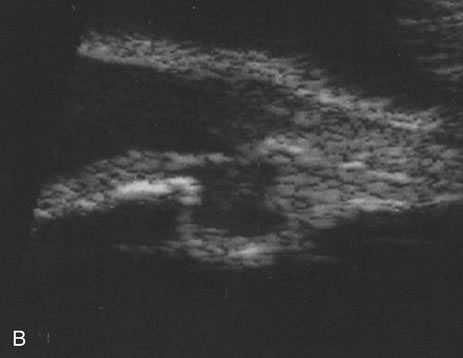

Iris melanomas can produce anterior chamber cell and flare, and if the tumor is located in the extreme iris periphery, it may be missed during a cursory examination. Iris melanomas, especially those in a circumferential or ring configuration, are often difficult to diagnose and may simulate either an anterior uveitis or glaucoma.16 Newer, higher-megahertz (high-frequency) ultrasound equipment is better for imaging anterior uveal tumors (Fig. 7).

Fig. 7. A. A typical iris tumor is easily visualized. Unfortunately, with atypical iris-ciliary body lesions, it may be difficult sometimes to differentiate different processes. B.A cystic change in a melanoma. On ultrasound, it is uncertain whether this is a benign or malignant lesion. Similarly, we are unable differentiate different types of neoplasms with this technique, and we have seen a few other anterior segment malignancies simulate melanoma on high-frequency ultrasound. Even with high-frequency ultrasound, we are unable to diagnose a “ring” melanoma.